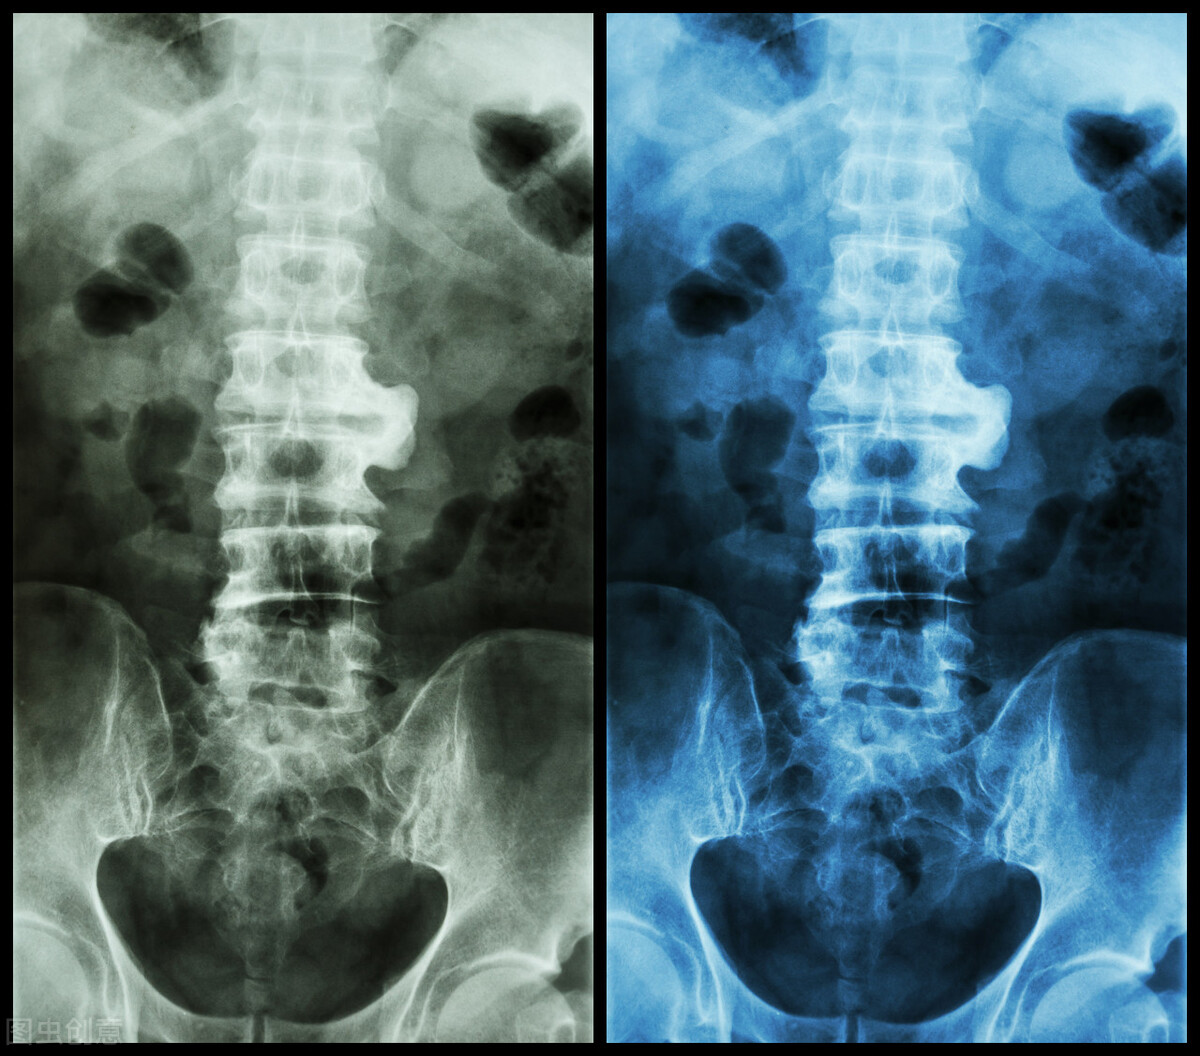

在日常生活中,很多人得了腰椎间盘突出都不知道为什么。明明平时也没干什么啊,怎么做个家务、正在运动、打个喷嚏……就突然腰椎间盘突出了呢?其实腰椎间盘突出并不是一种深不可测的骨病,那么导致腰间盘突出的有哪些病因呢?腰椎间盘突出后该如何选择治疗方案?今天给大家具体讲一下。

腰椎间盘突出治疗方案应如何选择

关于腰椎间盘突出的治疗方法还是不少的,倒是该如何选择呢,下面给大家讲一下保守治疗、微创治疗、手术治疗这三种治疗方法分辨有什么不同,希望能帮助大家选择更好的治疗方法。